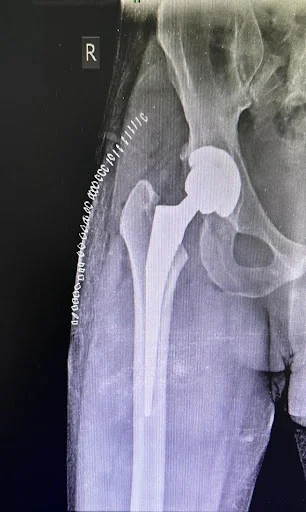

Hip Joint Prosthesis

Total Hip Replacement implants can be categorised into two broad segments:

1. Uncemented:

Both acetabular cup & femoral stem are implanted & stability is achieved through “Bone in-growth / on-growth” over Porous coating / HA coating on surface of implant.

Uncemented Stem

• Composition: Titanium Alloy (Tivanium / Beta Titanium Alloy)

• Surface Coating: Hydroxyapatite/ Porous coating, allowing bone growth onto its surface

Uncemented

• Consists of a shell made of titanium alloy with porous coated surface, allowing bone growth.

• Liner: Highly cross-linked polyethylene (XLPE) & Ceramic liners.